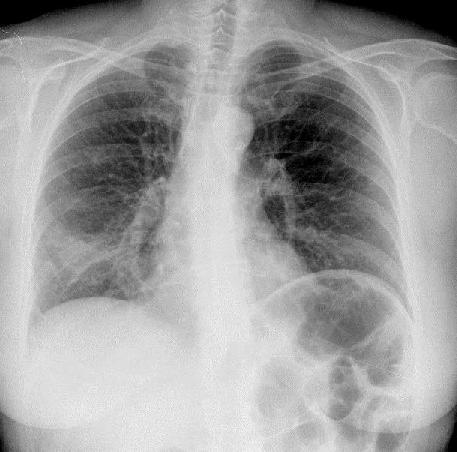

Tuberculosis

TBC signs:

1. Reticulo - Nodular

2. Apical + Parahilar

3. Uni- og Bilateral |